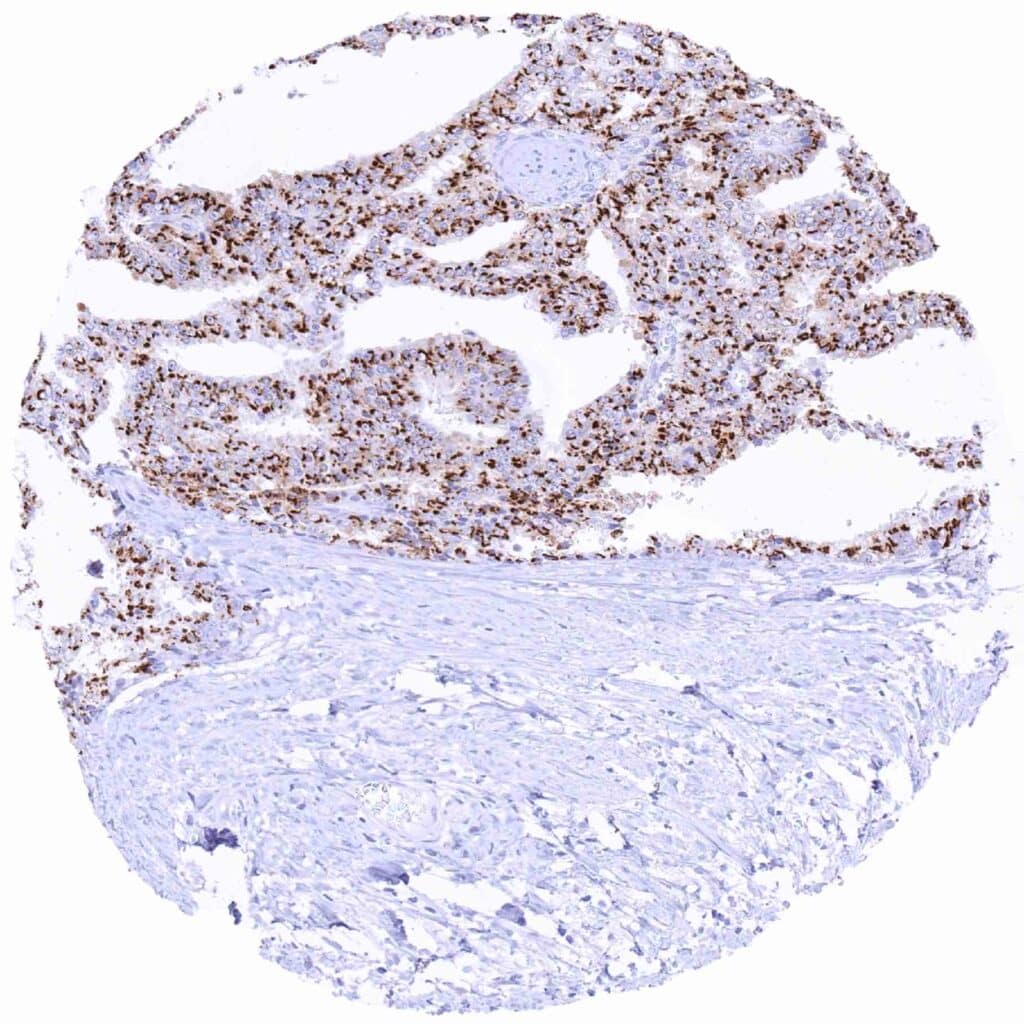

Prostate – Adenocarcinoma (Gleason 3+3=6) with strong Prostein immunostaining of tumor cells

Prostate – Adenocarcinoma (Gleason 3+3=6) with strong Prostein staining of tumor cells

Prostate – Adenocarcinoma (Gleason 4+4=8) exhibiting strong Prostein positivity of tumor cells

Prostate – Adenocarcinoma (Gleason 4+4=8) showing strong Prostein immunostaining of tumor cells

Prostate – Adenocarcinoma (Gleason 4+4=8) with strong Prostein positivity of all tumor cells

Prostate – Adenocarcinoma (Gleason 5+5=10) with strong Prostein immunostaining of tumor cells

Prostate – Adenocarcinoma (Gleason 5+5=10) with strong Prostein staining of all tumor cells